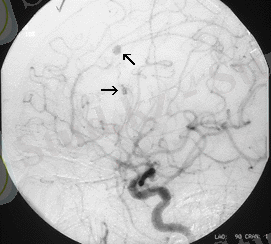

Диагностика: ЭЭГ, ЭхоЭГ, АГ, КТ, ЯМРТ алынған деректердің маңызы зор.